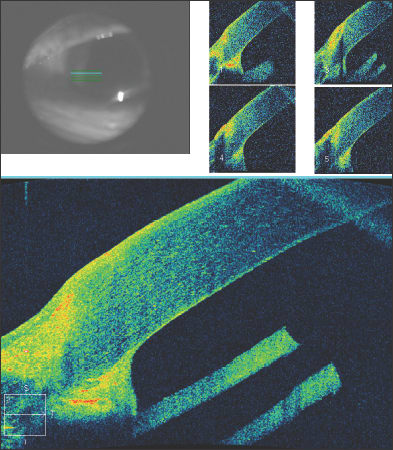

In Figure 5, a 45-year-old man is seen to have iridolenticular synechiae and an anterior polar cataract, using ASOCT. The anterior chamber angle can be identified, and these high resolution images often allow the identification of Schlemm's canal (Figure 6).

Figure 6. The anterior chamber angle in a patient with a narrow, but non-opposed, angle. Schlemm's canal can be visualized.